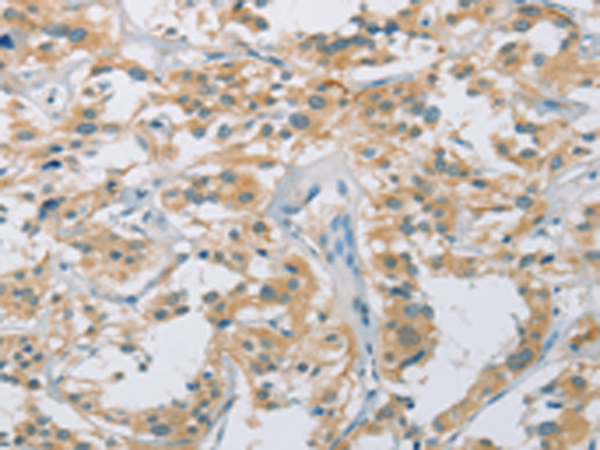

分类: 科研抗体货号: P08182别名: p38; CRKII应用: IHC反应种属: Human, Mouse, Rat